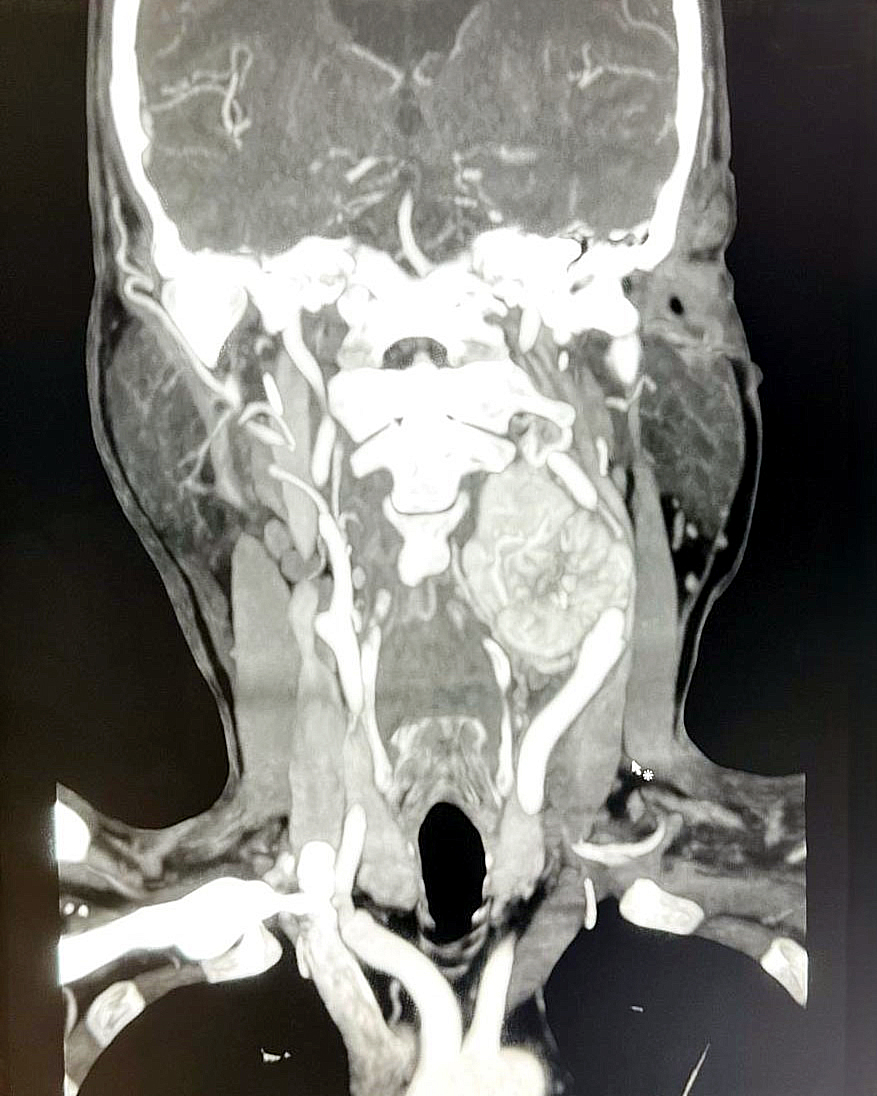

Un paciente de 55 años de edad fue sometido a un procedimiento quirúrgico en el servicio de Cirugía Vascular del Hospital Central, en donde le extrajeron un tumor denominado “Paraganglioma del Cuerpo Carotideo” también llamado PCC.

El Dr. Roberto Filizzola, jefe del servicio de Cirugía Vascular del Hospital Central señaló que “Primeramente, el paciente fue remitido a nuestra especialidad a través del servicio de Otorrinolaringología. El “Paraganglioma del Cuerpo Carotideo” contaba con 7 años de evolución, ya que es tumor que no produce dolor y es de lento crecimiento en la división de la arteria carótida del cuello”.

En la mayoría de los casos son benignos. Sin embargo, requieren de un diagnóstico y confirmación con estudios de imágenes y un tratamiento exhaustivo que generalmente implica la extirpación quirúrgica parcial o total.

Se procede a evaluar la extensión del tumor, su relación con las estructuras adyacentes, el suministro de sangre y de esa manera planificar la cirugía.